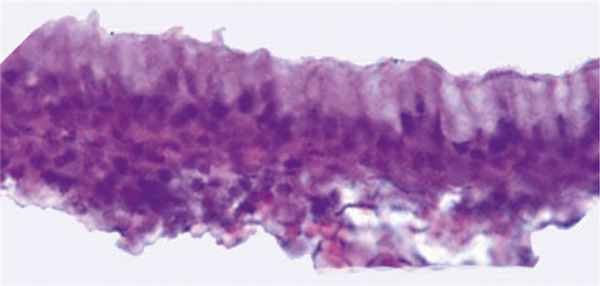

Карман, или сумка Торнвальдта, хорошо виден на рис. 1, 2. Новообразование

расположено в области верхнего констриктора глотки, выстлано слизистой оболочкой с мерцательным эпителием и представляется в виде кистоподобной или, так называемой, корковой формы, когда образовавшаяся в полости засохшая слизь периодически обтурирует одно или несколько выводных отверстий сумки (рис. 3).

Рис. 1. Компьютерная томография. Сумка (карман) Торнвальдта

На компьютерных и магнитно-резонансных томограммах киста Торн-вальдта выглядит как округлое, гиперэ-хогенная структура правильной формы с четкими контурами, не связанная с мышцами глотки. Это позволяет дифференцировать её с другими объемными процессами носоглотки, а именно ретен-ционными и бронхиальными кистами, злокачественными новообразованиями, превертебральными и заглоточными абсцессами, аденоидами.

Данная симптоматика может появиться у больного в любом возрасте, но чаще наблюдается у молодых людей. Учитывая неспецифичность клинических признаков заболевания, его диагностика, как правило, базируется на данных эндоскопического, лучевого и гистологического исследований. В типичных случаях при риноэндоскопии в задневерхнем отделе носоглотки определяется плотное, округлое образование с четкими контурами, содержащее воспалительный экссудат [13]. При рентгенологическом исследовании (компьютерная и магнитно-резонансная томографии) киста выглядит как округлое гиперэхогенное образование правильной формы с четкими контурами, не связанное с мышцами глотки [14, 15].

В типичных случаях при эндориноскопии в задневерхних отделах носоглотки определяется плотное, напряженное, гиперемированное, округлое образование с четкими контурами, содержащее воспалительный экссудат. На компьютерных и магнитно-резонансных томограммах киста Торнвальдта выглядит как округлое, гиперэхогенное образование правильной формы, с четкими контурами, не связанное с мышцами глотки. Это позволяет дифференцировать её с другими объемными процессами носоглотки, в частности, с интрааденоидными, ретенционными кистами, злокачественными новообразованиями носоглотки, превертебральными и заглоточными абсцессами, хоанальным полипом, которые на томографических срезах имеют другую конфигурацию.